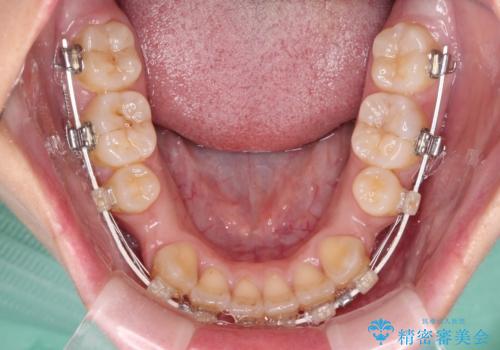

- 矯正装置

- 審美装置

奥歯の咬み合わせが理想的であり、歯の移動に時間のかかる出っ歯でもなかったため、2年程度で治療を終えることを目標としましたが、無事に予定通りの2年間で終えることができました。